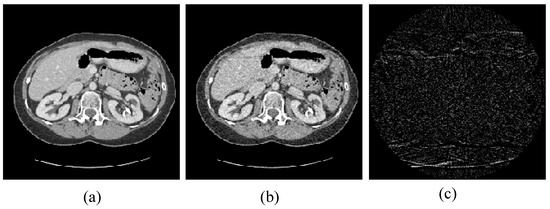

Figure 1. Pelvic image for the experiments: (a) the target image; (b) the prior image; and (c) the difference image between the prior image and the target image.

4.1. Image Reconstruction Experiment of Pelvic Image

The first image reconstruction experiment is using a pelvic image to show the feasibility of our algorithm for SVCT reconstruction, as shown in Figure 1. We extracted 80, 64, and 48 views from a full scan and selected parameters empirically. The parameters are set as follows: a = 0.5, γ1 = 0.3, and γ2 = 0.08. Figure 2, Figure 3 and Figure 4 show the ground truth and reconstruction images via FBP, OS-SART, TV, PICCS, TVPI-G, and our method NPICCS. From these figures, it is evident that our algorithm outperforms the other methods in terms of recovering image structures and suppressing noise. Specifically, the FBP and OS-SART results (as shown in Figure 2b,c, Figure 3b,c and Figure 4b,c) contain high levels of noise and artifacts, while TV results (as shown in Figure 2d, Figure 3d and Figure 4d) are characterized by blurring and staircasing effects. The PICCS and TVPI-G methods provide better results than the other approaches because of the introduction of prior information, but image edges are missing as shown in Figure 2e,f, Figure 3e,f and Figure 4e,f. At the same time, it can be seen that our method is able to preserve image edges and suppress noise effectively, as shown in Figure 2g, Figure 3g and Figure 4g.